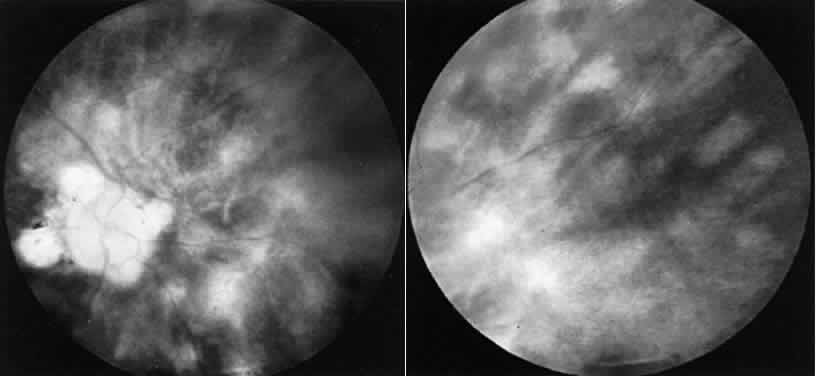

tests were normal. CASE 3 (FIG. 10). A 57-year-old female was referred because of increasing complaints of

difficulty with her night vision and her side vision. She had a long history

of low-grade uveitis and a progressive decrease in central vision. Visual

acuity 20/100 OD, 20/80 OS. The vitreous showed multiple small

cells. Both retinas showed narrowed arterioles and strands of pigment

in the far periphery. Multiple areas of atrophy of the RPE were seen

throughout. An ERG was extinguished.  Fig. 10. Case 3. Left. Posterior pole. Right. Peripheral retina. See text for details. Fig. 10. Case 3. Left. Posterior pole. Right. Peripheral retina. See text for details.

|

This patient had birdshot choroiditis, an inflammatory disorder of the

choroid with severe secondary photoreceptor degeneration. The ERG gives

evidence of widespread degeneration, but the history and clinical findings

preclude the diagnosis of a generalized heredoretinal degeneration. This

disorder of birdshot choroiditis may produce a “pseudo-retinitis

pigmentosa” picture8 (Table 2). TABLE 2. Pseudoretinitis Pigmentosa